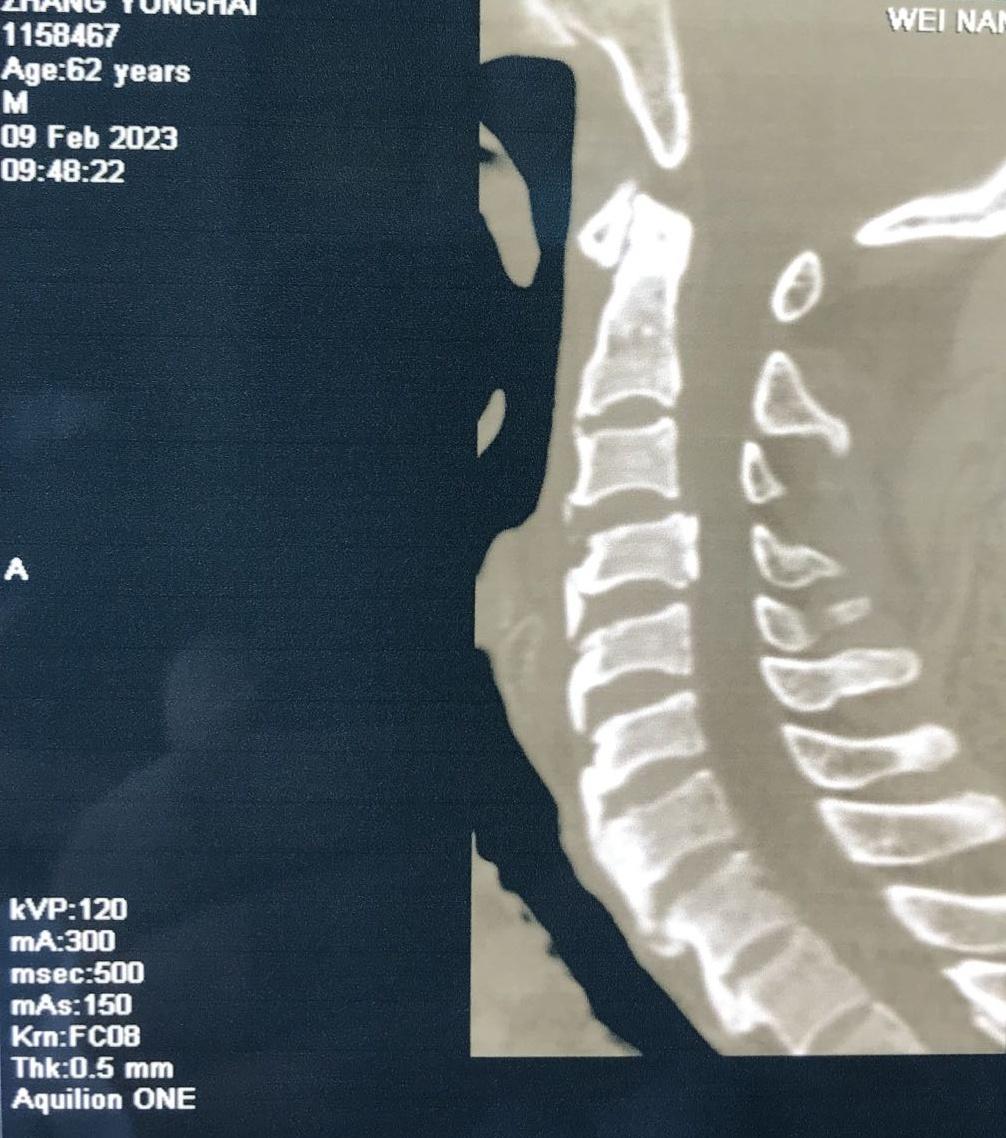

近日,一位颈部外伤合并肢体瘫痪症状患者来到乐鱼在线登录入口骨一科就诊。经入院后紧急检查,发现患者为颈3.4椎体骨折、脱位,并有右后侧关节突关节骨折、绞索,四肢肌力约3级。

入院后,科室立即进行常规术前检查,给予8公斤大重量颈枕带牵引,但因关节脱位的绞索,颈椎复位困难。几日后,患者在牵引过程中出现右上肢抽痛加重,肌力减低表现。紧急时刻,骨一科决定立即为患者行急诊手术治疗。

经过有序准备,为患者先行颈后路减压,解锁关节突绞索,牵引复位,使用颈椎侧块螺钉固定,同时椎板间植骨融合。随后再将患者转为仰卧位,再行颈前路脱位椎体的间盘摘除,融合器植入,钢板螺钉固定,历时3小时,顺利结束。患者术后恢复良好,肢体功能状态较术前改善显著,上肢抽痛症状消失,肌力已达4-5级,患者及家属对治疗效果颇为满意。